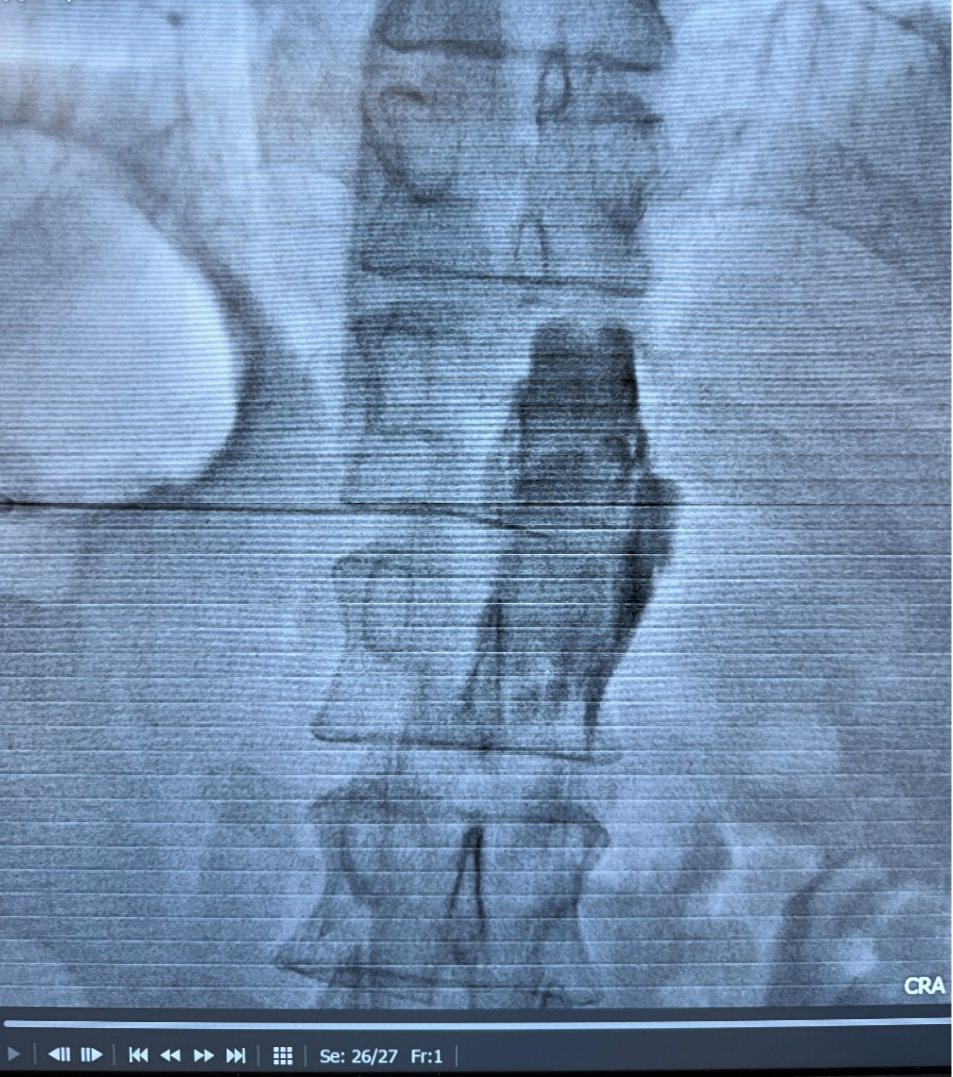

腹腔神经丛毁损术,堪称上腹部癌痛的“定点清除术”。医生在CT与超声影像的双重引导下,将一根细针精准送达传递疼痛信号的腹腔神经丛,注入少量神经毁损药物,即可长期阻断痛觉传导通路。

“这项技术的核心就是‘精准’,”医生解释道,“不用像口服药那样走全身血液循环的‘远路’,直接对准疼痛的‘信号指挥部’下手,实现‘釜底抽薪’式镇痛。”

腹腔神经丛是人体上腹部最大的自主神经网络,像是一个管理上腹脏器疼痛信号的“交通总枢纽”。毁损术即通过穿刺技术,用乙醇等化学药物精准地、永久地阻断这个枢纽的信号传导,从而实现长期镇痛。